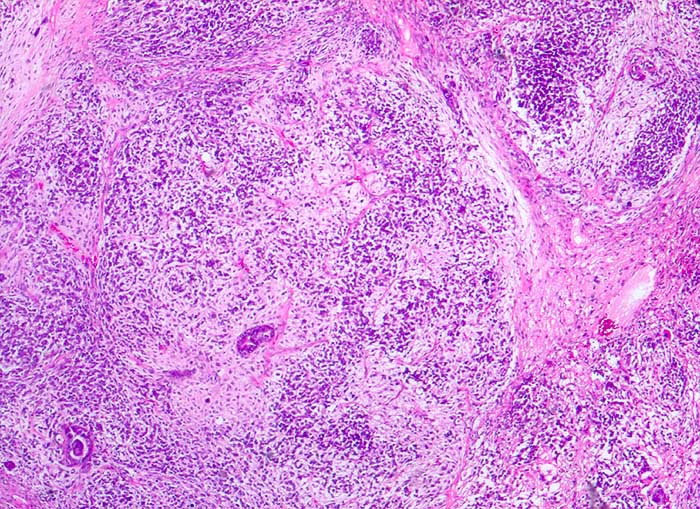

Maligner Müllerscher Mischtumor des Ovars

Müllersche Mischtumoren bestehen aus einer epithelialen und einer mesenchymalen Komponente. Die epitheliale Komponente ist in der Regel ein Adenokarzinom. Die Sarkomkomponente kann homolog (Leiomyosarkom, Stromasarkom, Fibrosarkom) oder heterolog (Rhabdomyosarkom, Chondrosarkom...) sein also nicht aus ortsständigem Mesenchym entstammend. Am häufigsten treten diese Tumoren im Uteruscavum auf. Sie können aber auch in anderen Lokalisationen des Genitaltrakts vorkommen. Die Ausstriche enthalten ein buntes Zellbild mit deutlich atypischen Zellen. Wenn neben Karzinomzellen auch atypische mesenchymale Zellen vorhanden sind, kann zytologisch die Diagnose eines malignen Müllerschen Mischtumors gestellt werden.